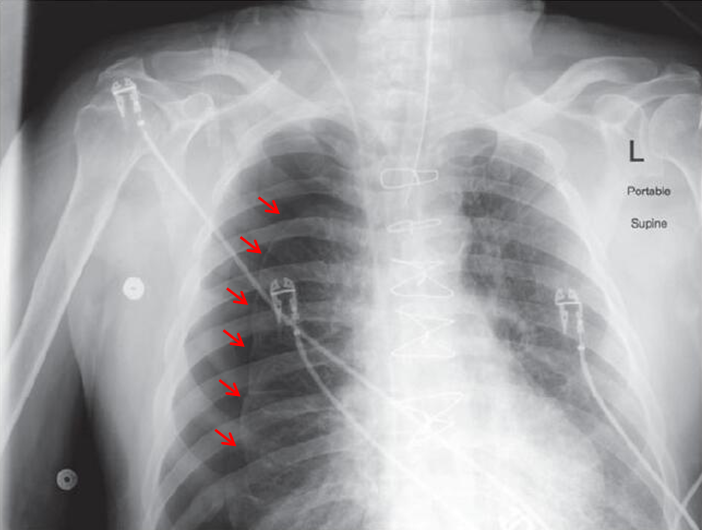

带着这些疑问,重新审视这个病例,肺部听诊时发现右肺呼吸音减低,心音清楚,心律齐,未闻及P2亢进,各瓣膜听诊区未闻及杂音。立即完善床旁胸片,提示右侧大量气胸

图2 床旁胸片提示右侧大量气胸,红色箭头指示气胸线